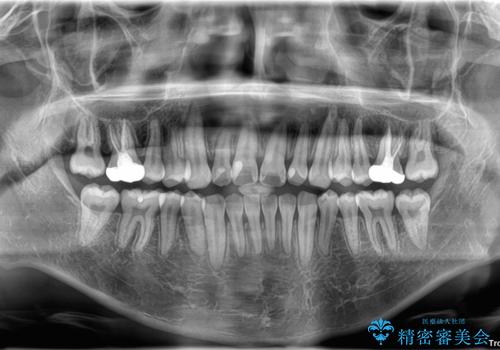

適切な診断と装置の選択により、1年という短期間でここまで改善できます。

見た目の美しさだけでなく、将来のむし歯や歯周病リスクを減らすことにもつながる治療です。